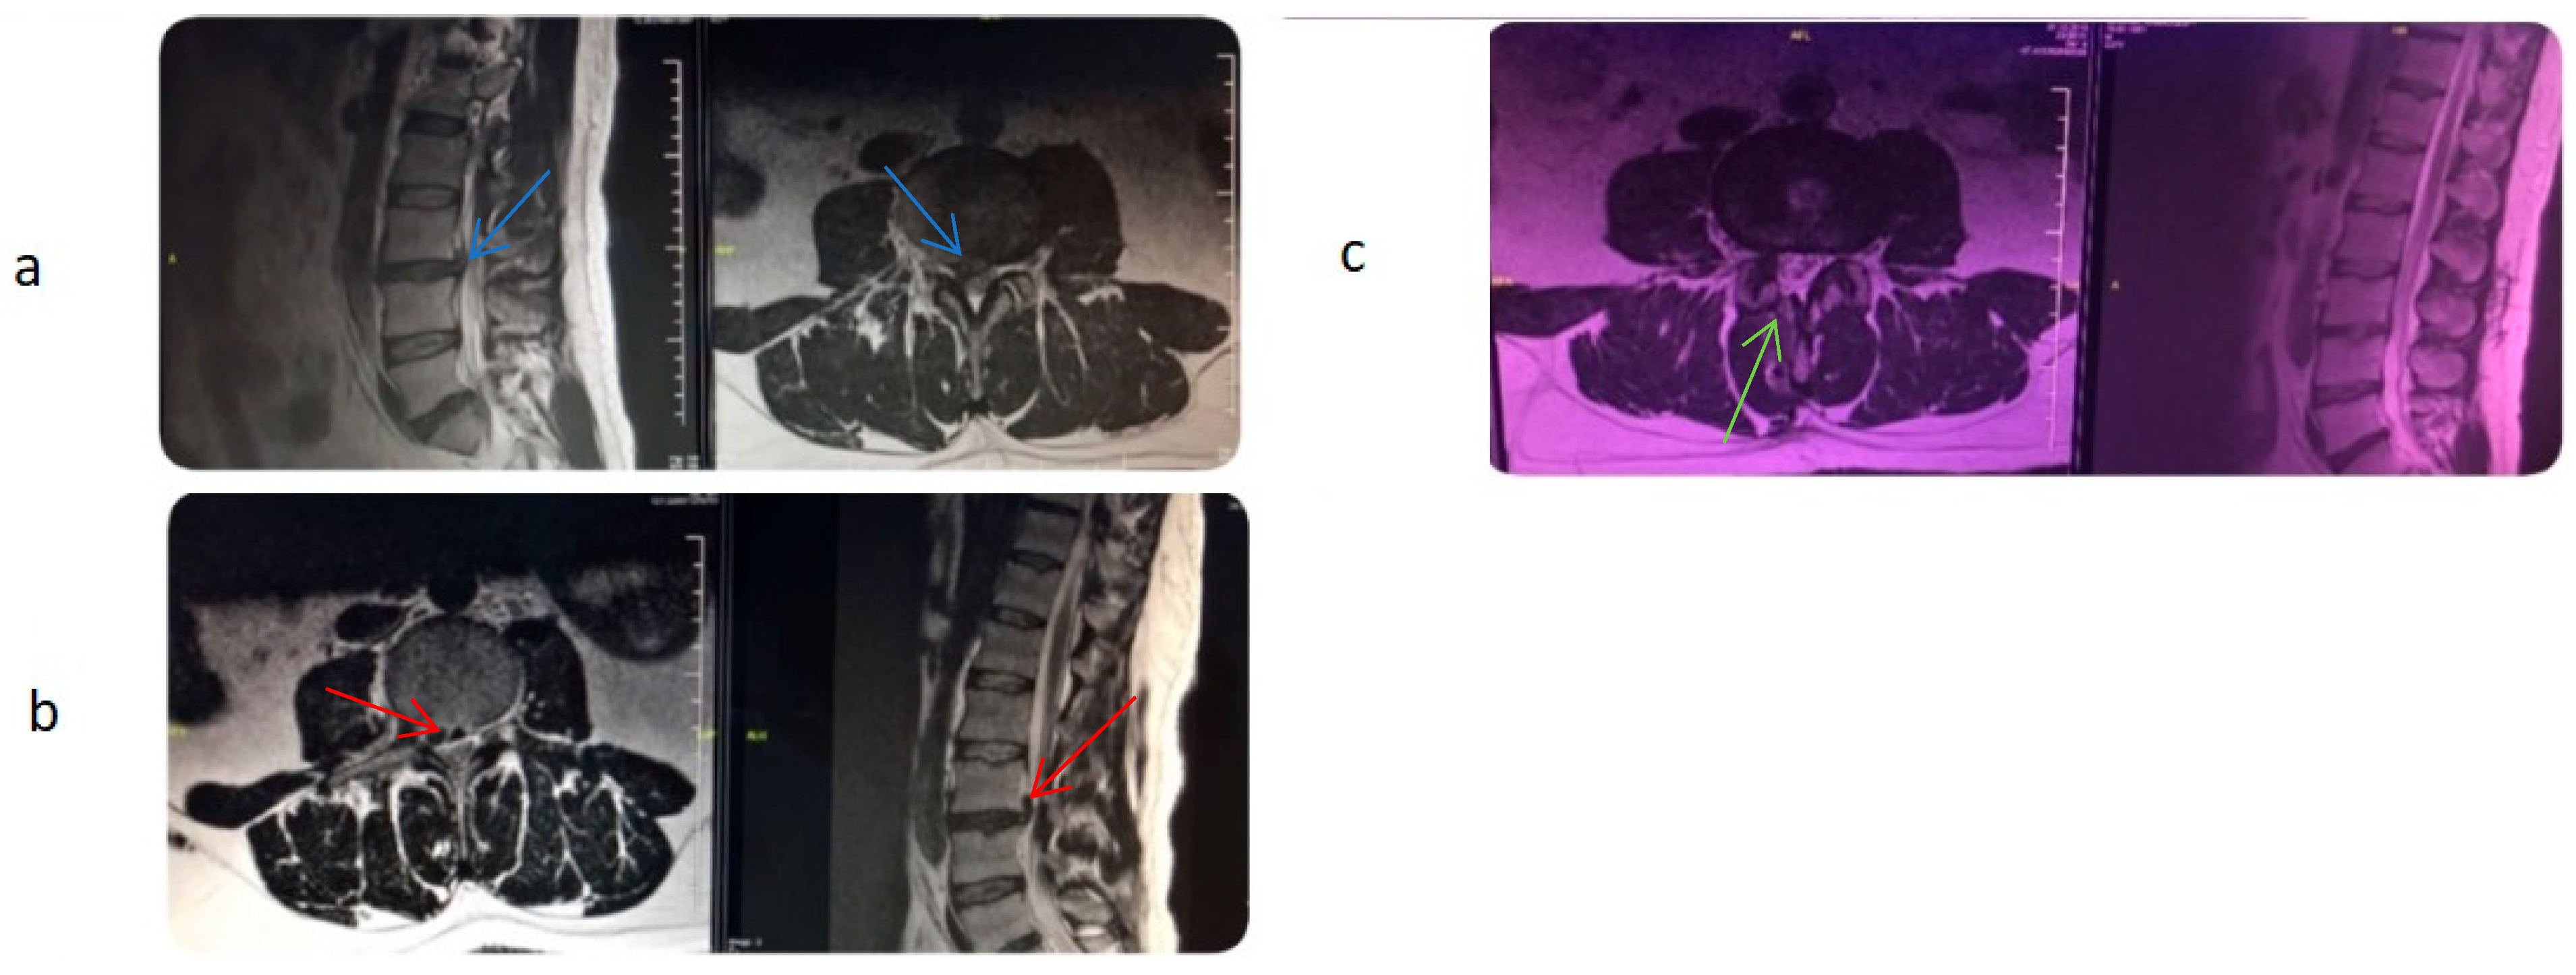

2.4. Surgical Technique

The epiduroscopy surgical technique was performed under sterile operating room conditions with hemodynamic and respiratory monitoring, following the administration of preoperative antibiotics. Communication with the patient was maintained during the procedure, and deep sedation was avoided to ensure full neurological monitoring [17]. Before the procedure, the caudal and sacral areas were wiped with an antiseptic solution. Local anesthetics were administered to the skin and subcutaneous tissue. A skin incision was made above the sacral hiatus. A trocar was inserted through the incision site into the sacrum, and C-arm fluoroscopy was used to confirm that the trocar was in the midline with lateral and anteroposterior views. Then, a Spinnaut-V video-guided catheter (IMEDICOM Co., Ltd., Gunpo, Republic of Korea) was inserted into the trocar. The V video-guided catheter was manipulated into the anterior epidural space at the level of S2–S4 vertebrae with a fluoroscopic lateral view. An anterior epidurogram was performed using a non-ionic contrast agent to visualize the dyeing of the anterior epidural space and the outline of its pathology (Figure 1).

The vertebral level where the catheter tip was located was determined with fluoroscopy. Mechanical adhesiolysis was performed with a directable video-guided catheter that was washed with saline through the side arm of the cannula for better visualization. The L5-S1, L4-5, and L3-4 levels were viewed using video imaging. Although the procedure is initiated via the sacral hiatus, the flexible video-guided catheter allows advancement cranially up to the L3-L4 level under fluoroscopic guidance. This enables visualization and treatment of upper lumbar disc herniations through the sacral approach. After the herniated disc pathology was observed, a 400 µm diameter Ho: YAG laser probe (ACCU-Tech Co., Ltd., Beijing, China) was advanced to the tip of the video-guided catheter. The lateral view and catheter placement (within the posterior longitudinal ligament [PLL] at the lowest level of the target disc) were confirmed with fluoroscopy and epiduroscopy, aided by video imaging of the anterior epidural space. Using the Ho:YAG laser at 5 W (0.5 J, 10 Hz), a hole was made in the PLL. Then, a fibre video cable was inserted under the herniated intervertebral disc through the hole in the PLL, and the herniated disc was ablated using the Ho:YAG laser at 8 W (0.8 J, 10 Hz). The decompression of the ruptured disc was subsequently confirmed epiduroscopically, demonstrating its decompression from the nerve root (Figure 2). Although standardized laser settings were attempted, some variability occurred because of tissue density and anatomical constraints. At the end of the procedure, 16 mg dexamethasone was applied to the epidural region, and then, the catheter was removed. All procedures were performed by the same clinician, who had at least five years of experience in interventional pain management and had received specialized training in SELD. The patients without any complaints were sent to a postoperative care room [18].

Figure 1. (A) A pre-procedure epidurogram obtained before performing SELD highlights the herniated nucleus pulposus and adhesions causing flow obstruction at the affected level. (B) A post-procedure epidurogram following SELD demonstrates a reduced herniation outline and restored flow at the previously affected site. (Green star: tip of the catheter (in the anterior epidural space); green arrow: posterior epidural contrast distribution. Blue arrow: spread of contrast medium into the anterior epidural space after adhesiolysis).